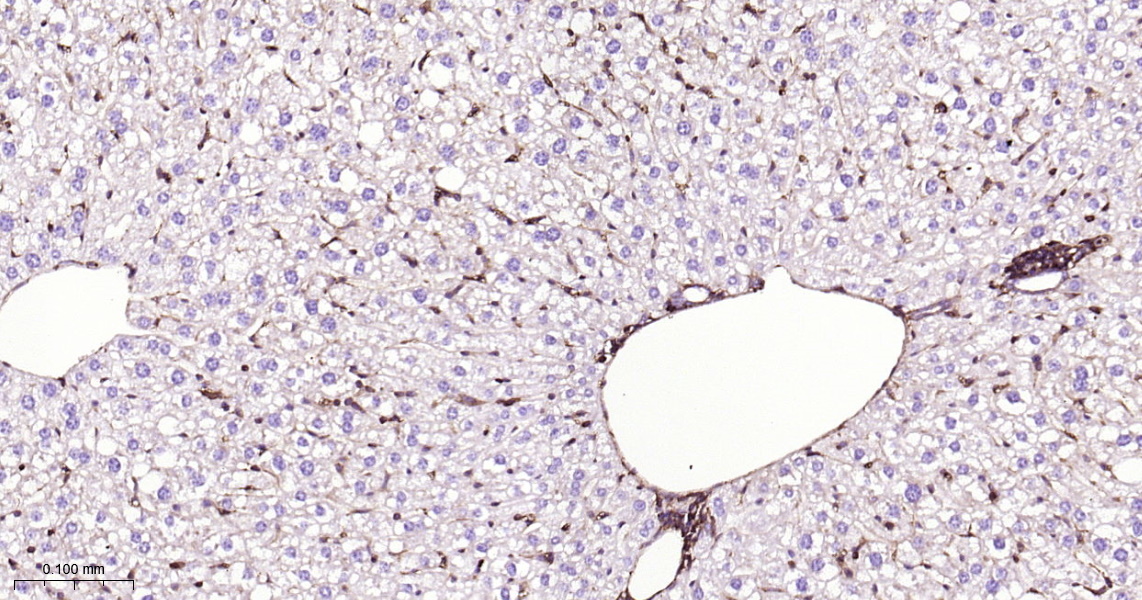

• IHC-P

IHC-P IHC-P1:100-500